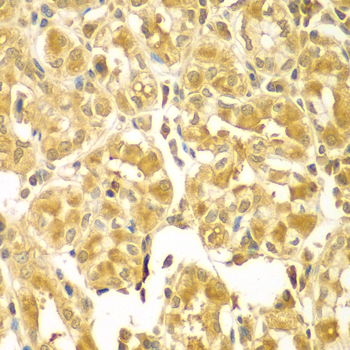

Immunohistochemistry of paraffin-embedded human gastric using SESN2 antibody at dilution of 1:100 (x400 lens).

This gene encodes a member of the sestrin family of PA26-related proteins. The encoded protein may function in the regulation of cell growth and survival. This protein may be involved in cellular response to different stress conditions.